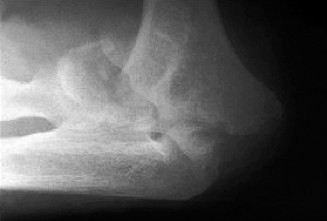

any activity in which the arm is extended and externally rotated while under maximal contraction (eccentric loading force). Patients often present with pain, swelling, ecchymosis, weakness and loss of the axillary fold in the acute setting. In the chronic setting, the swelling and ecchymosis have typically subsided. They may report an audible pop or a tearing sensation. On examination, there can be an apparent continuous muscle or tendon that is mistaken for an intact PMM tendon, but this represents the fascia of the PMM that is continuous with the fascia of both the brachium and the medial antebrachial septum. This continuous fascia will examine as a cord-like structure as shown in Figure 2–78.

Figure 2–78